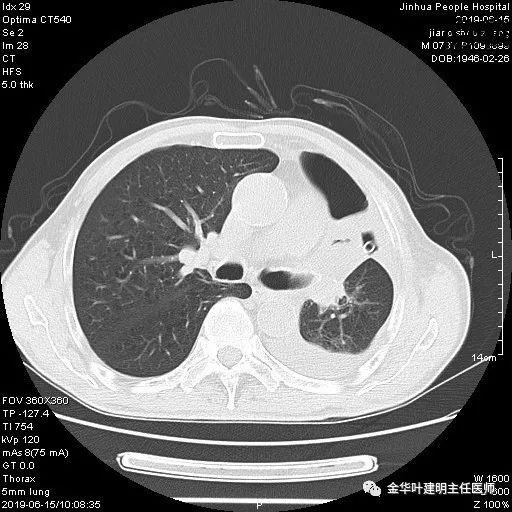

6.15上午:24小时胸管引流出血性液250ml;复查胸部CT示: